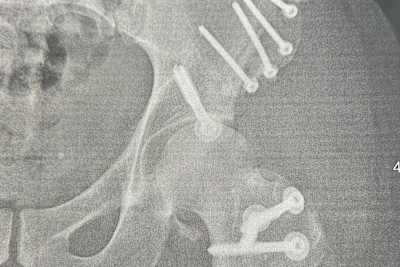

Gute Nachrichten gab es für ihn bei einem kürzlichen Kontrolltermin, bei dem die Hüfte gecheckt wurde. "Der Heilungsverlauf sieht gut aus. Die Schrauben sitzen gut und es befindet sich alles noch dort, wo es hingehört", berichtete Dilger. "Aktuell darf ich die Hüfte und das Bein mit 20 kg belasten und ab jetzt die Belastung um wöchentlich 10 kg steigern." Der gute und planmäßige Heilungsverlauf eröffnet neue Möglichkeiten in der Reha und für die Rückkehr aufs Motorrad. "Der weitere Saisonverlauf ist offen", so der 33-Jährige. "Ich kann endlich voll mit der Physiotherapie beginnen, da das Bein jetzt vollumfänglich bewegt werden kann. In etwa vier Wochen werde ich das Bein voll belasten können, dann sieht man weiter."